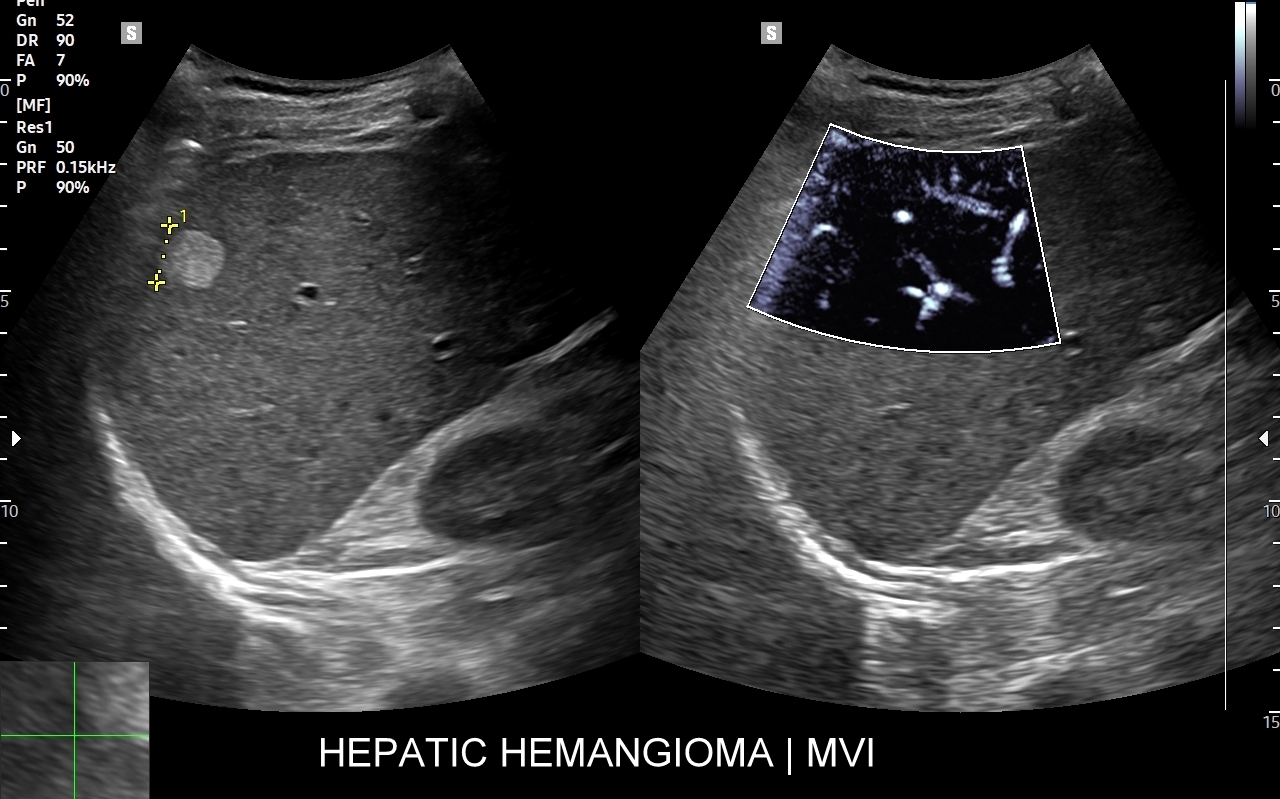

Rozwinięciem standardowego badania USG jamy brzusznej jest badanie multiparametryczne MPUS (ang. multiparametric ultrasound), w ramach którego wykorzystuje się różnorodne, nowoczesne modalności sonograficzne, takie jak tryby mikrounaczynienia MVI, B-flow, elastografię, ilościową ocenę stłuszczenia wątroby QUS, czy tryb Dopplera spektralnego, a to wszystko w celu uzyskania dodatkowej oceny funkcjonalnej i biologicznej struktur, narządów oraz tkanek jamy brzusznej. Obrazowanie MPUS niejednokrotnie poprawia także wizualną ocenę narządów wewnętrznych, czego przykładem jest zastosowanie trybu MVI w ramach bezkontrastowej angiografii sonograficznej naczyń oraz w ocenie guzów nerek. Klasycznymi i najczęstszymi zastosowaniami badania MPUS są jednakże funkcjonalna ocena wątroby w kierunku stłuszczenia, zwłóknienia, zapalenia i nadciśnienia wrotnego, a także ocena żywotności i funkcji nerek.

• Możliwość rozszerzenia zakresu badania USG w razie wystąpienia konieczności. Praktycznymi przykładami są zastosowanie trybu MVI w przypadku wykrycia guzka w nerce, czy przeprowadzenie badania elastograficznego i dopplerowskiego w wypadku stwierdzenia nieprawidłowego obrazu wątroby.